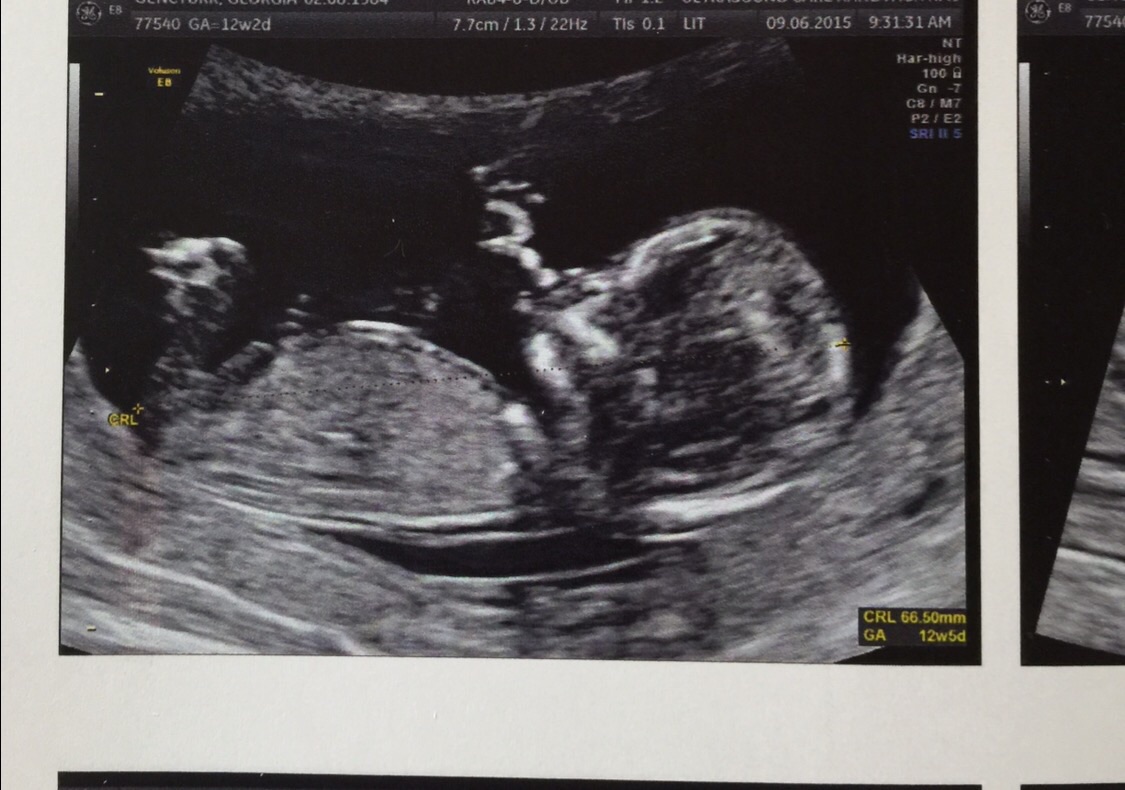

Any guesses would be appreciated, I've attached my 12 week potty shot xx:baby2:

If this is very close to 12w0d I would only put my guess at 60% for boy, If this is closer to 13 weeks, I get more confident boy.

Maybe boy? Post all pics you have, also side view/nub shots.

Too early to tell from a 12+2 potty shot. Was thinking girl from the other picture but now seeing two areas which could be nubs. Maybe boy 60/40. Sorry, any other piccies?

A very slight boy lean from me. GL!